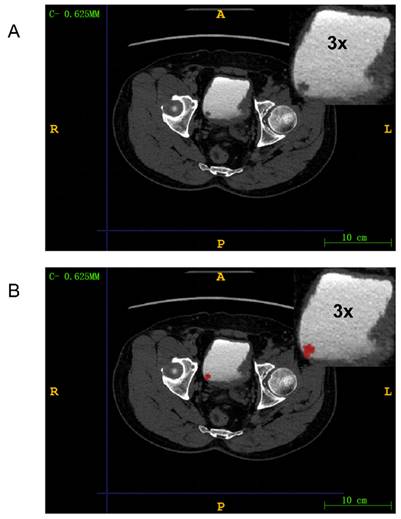

We used ITK-SNAP (version 3.8.0) to manually delineate regions of interests (ROIs) around lesions in DICOM images. A radiologist with 15 years of experience reviewed and confirmed the manually delineated ROIs to ensure they encompassed tumor tissue for radiomic feature extraction (Figure 3). The medical images in DICOM (.dcm) format were then converted to NIfTI (.nii) format.

Figure 3

Mapping ROI areas. (A) Imaging information of bladder cancer; (B) Outline of bladder cancer: Red region is bladder cancer. The upper right corner part is an enlarged image of the bladder tumor by three times.

We used Pyradiomics (version 3.1.0) to extract 975 radiomic features from the ROIs. (Table S1) This package is available on GitHub[18]. The extracted features included shape features, first-order statistics, gray level co-occurrence matrix (GLCM), gray level run length matrix (GLRLM), gray level size zone matrix (GLSZM), and gray level dependence matrix (GLDM). The radiomic features were automatically extracted by the Pyradiomics package and saved as comma-separated values files. The example of HER2 expression being negative and positive in CTU images can be found in Figure S2.